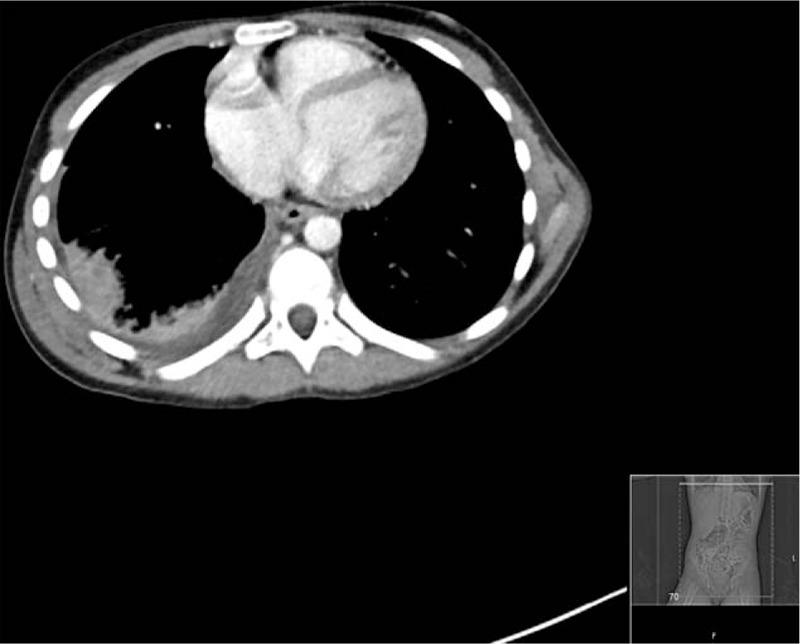

We describe the unique case of a child with pneumonia presenting with acute scoliosis and abdominal pain, without any typical features of the disease.A 10-year-old girl presented to the emergency department on 3 consecutive days with right-sided abdominal pain. There were no associated features, in particular, no fevers or respiratory symptoms. On the first 2 presentations, observation,examination, and blood test findings were unremarkable. Chest x-ray and abdominal ultrasound were also normal. On the third presentation a marked scoliosis was noted and abdominal examination revealed right-sided tenderness with rebound. The patient was admitted and a computed tomographic scan of the abdomen arranged. Unexpectedly, this revealed a right lower lobe pneumonia and associated pleural effusion. Despite treatment, the parapneumonic effusion enlarged rapidly and she developed respiratory distress, necessitating transfer to a tertiary centre.The diagnosis of pneumonia can be challenging because of a lack of respiratory signs, the masking of systemic features by antipyretic effects of first-line analgesics, and a high rate of false-negative chest radiographs. The development of acute scoliosis should lead the clinician to strongly consider pneumonia in such circumstances.

我们描述了一例独特的病例,一名患有肺炎的儿童出现急性脊柱侧弯和腹痛,无该疾病的任何典型特征。一名10岁女孩连续三天因右侧腹痛到急诊科就诊。无相关特征,特别是无发热或呼吸道症状。在前两次就诊时,观察、检查及血液检查结果均无异常。胸部X光和腹部超声也均正常。第三次就诊时发现明显的脊柱侧弯,腹部检查显示右侧有压痛及反跳痛。患者入院并安排了腹部计算机断层扫描。出乎意料的是,扫描显示右下叶肺炎及相关胸腔积液。尽管进行了治疗,肺炎旁积液仍迅速增大,她出现了呼吸窘迫,因此需要转至三级医疗中心。由于缺乏呼吸道体征、一线镇痛药的退热作用掩盖了全身特征以及胸部X光片假阴性率高,肺炎的诊断可能具有挑战性。在这种情况下,急性脊柱侧弯的出现应促使临床医生高度怀疑肺炎。